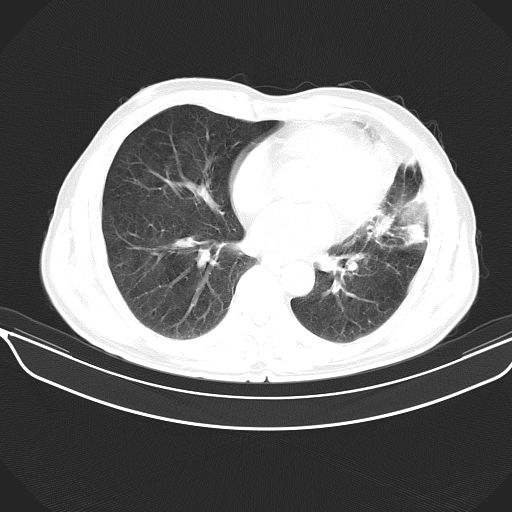

以下是引用心路寻觅在2010-3-1 10:23:00的发言:[br]1、考虑左肺上叶周围型肺癌[br]2、右上肺陈旧性病灶。[br][br][本贴已被 心路寻觅 于 2010-3-1 10:40:18 修改过]

以下是引用shuiyuan在2010-3-1 10:45:00的发言:[br]考虑左肺上叶中心型肺癌伴阻塞型炎症,邻近胸膜受侵。